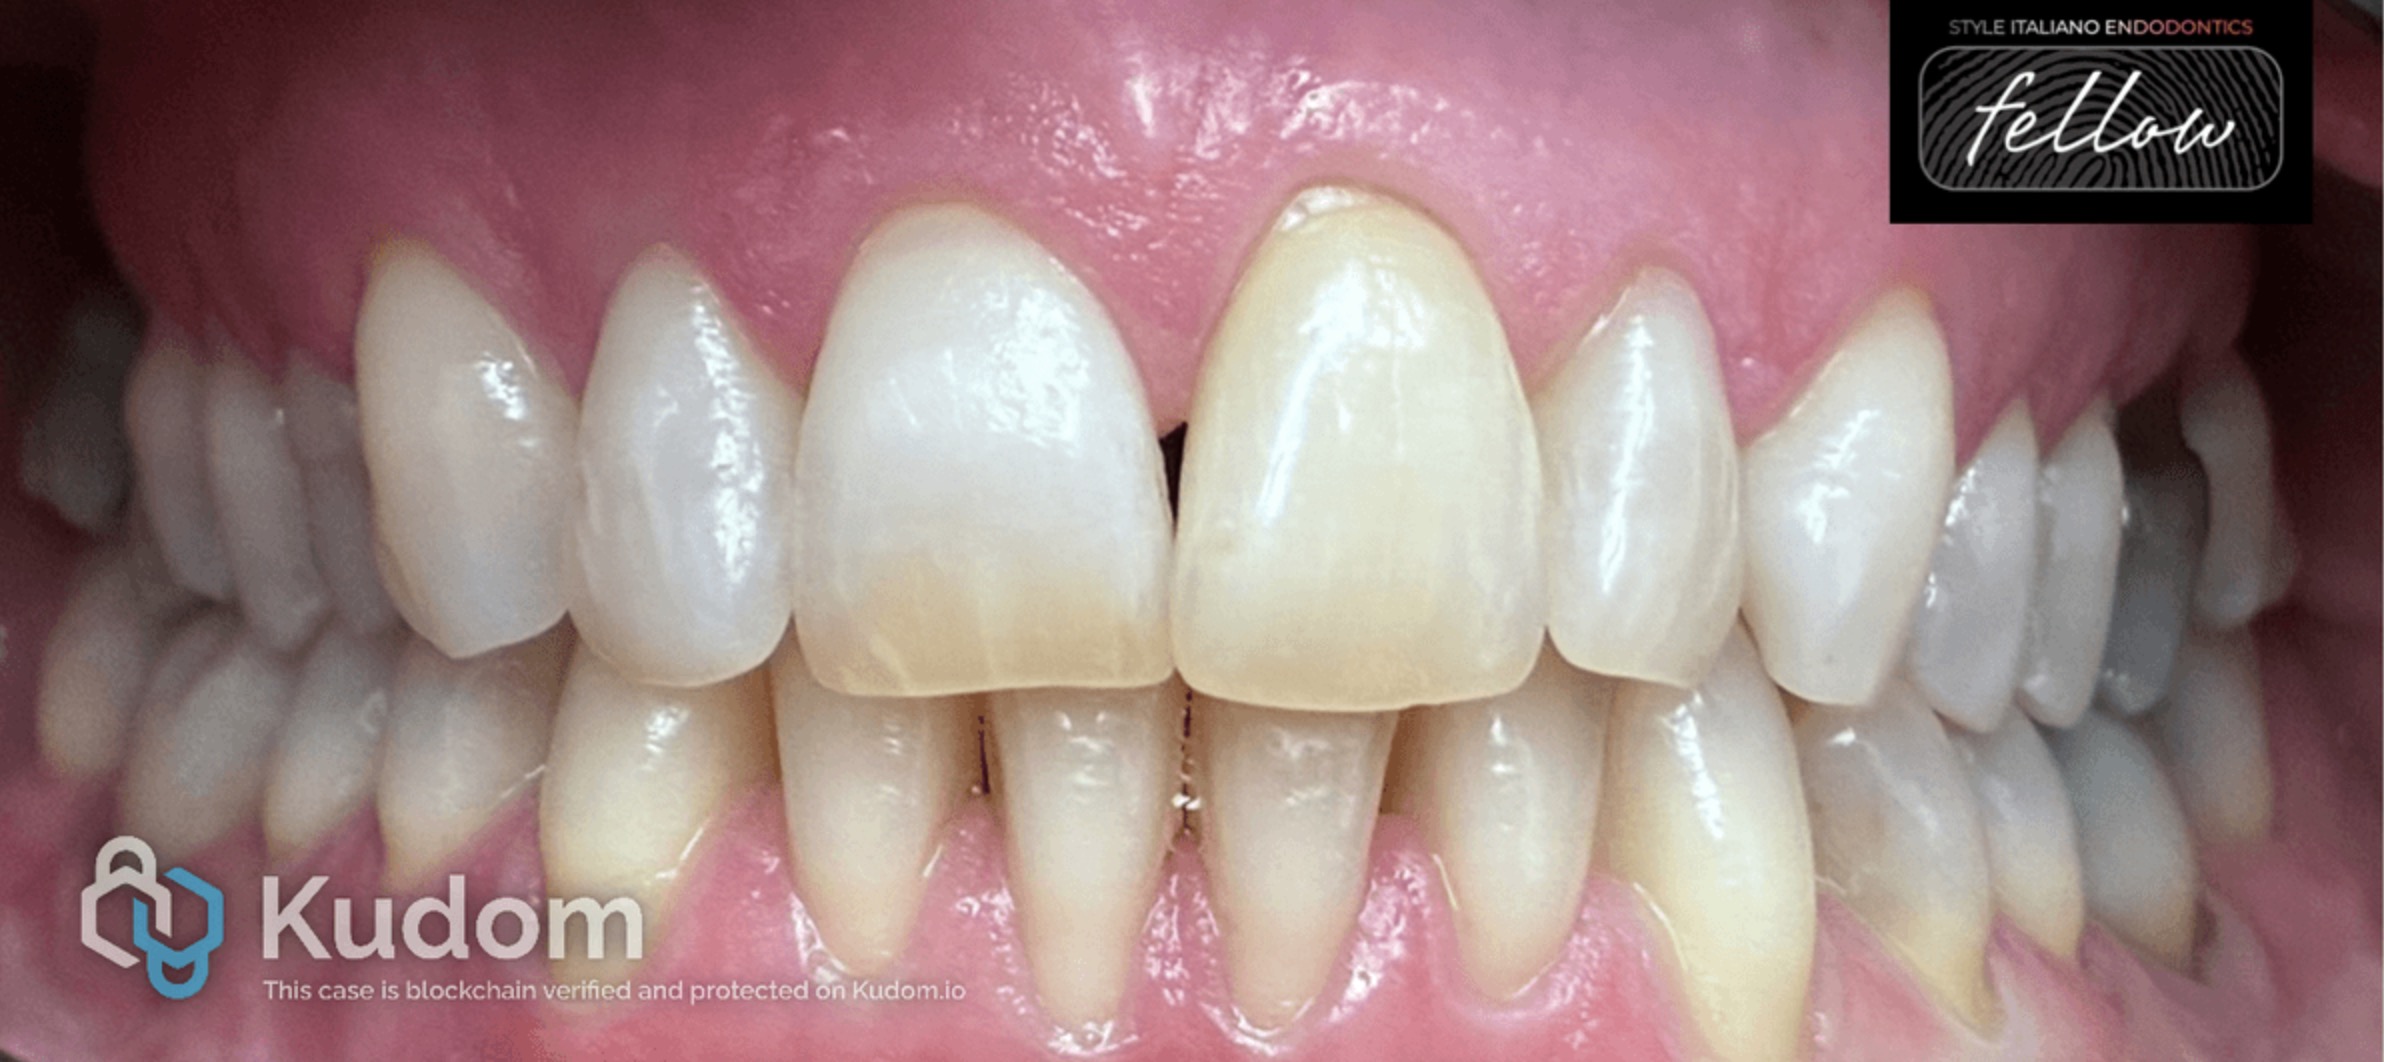

Fig. 1

A female patient presented with discoloration of tooth 21 and a history of dental trauma during childhood. The tooth was asymptomatic, with no clinical or radiographic signs of endodontic pathology. Pulp vitality testing performed with ethyl chloride confirmed the absence of vitality.